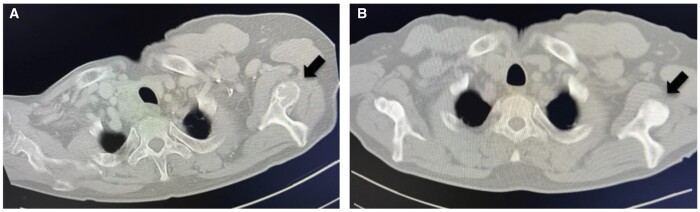

We present two rare cases of parathyroid carcinomas associated with multiple brown tumours. Plain radiographs, computed tomography, and neck ultrasonography revealed the presence of bone and parathyroid tumours. Despite the use of 99m Tc-methoxy isobutyl isonitrile (99mTc-MIBI) or 18F-fluorodeoxyglucose-positron emission tomography (18F-FDG PET)/CT, it was difficult to differentiate bone metastases from brown tumours. Parathyroid carcinoma was confirmed by histopathological examination following parathyroidectomy, resulting in spontaneous bone lesion improvement. In patients with parathyroid carcinoma presenting with bone lesions suggestive of metastasis, understanding the potential for brown tumour accumulation through 99mTc-MIBI or 18F-FDG PET/CT is pivotal. With this understanding, it is possible to diagnose brown tumours with parathyroidectomy and follow up for improvement of bone lesion and avoid invasive biopsy or surgery.